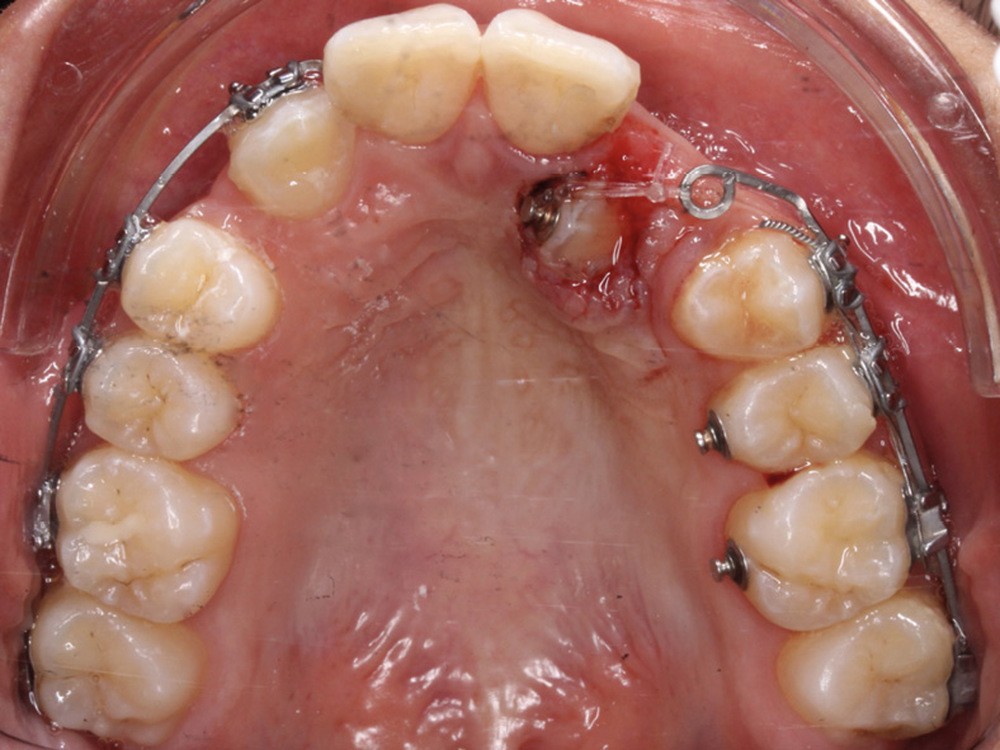

La désinclusion des canines a été réalisée dans un deuxième temps opératoire après trois semaines de cicatrisation muqueuse afin d’avoir une quantité de gencive attachée suffisante lors de la réalisation des lambeaux. Un lambeau déplacé apicalement a été réalisé pour désinclure la 13, avec une direction de traction distale sur une potence soudée sur le sectionnel activée après trois semaines de cicatrisation (fig. 3). Un lambeau muco-périosté repositionné a été réalisé pour désinclure la 23 qui a été immédiatement mise en charge par traction distale sur un bouton palatin collé sur 25. Un approfondissement vestibulaire mandibulaire antérieur a ensuite été réalisé.

La traction des canines incluses s’est faite sur des sectionnels postérieurs en TMA .017 x .025 de type Ballista (fig. 4a,b). Un décapuchonnage de la 23 a dû être réalisé pour lui permettre de transpercer la muqueuse palatine. Des cales occlusales ont été ajoutées pour assurer le passage de la canine de la situation palatine à vestibulaire. Un contrôle radiologique a permis de suivre la traction. Parallèlement, la fermeture des espaces mandibulaires s’est faite par perte d’ancrage postérieure et par redressement antérieur grâce à des chaînettes élastomériques.